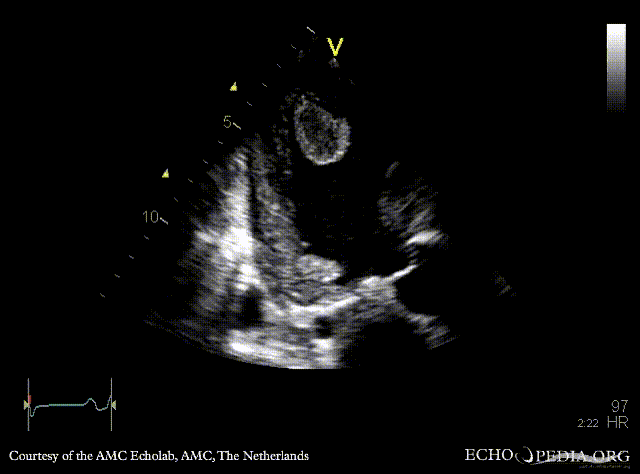

Case 142